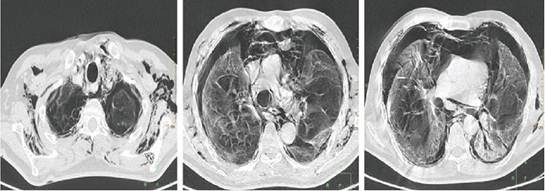

Debido a esto se decide tomografía urgente de control, la cual mostró un neumotórax bilateral de grado moderado asociado a un importante neumomediastino, enfisema subcutáneo en partes blandas de cuello y regiones escapulares, colapso parcial no mayor al 70% de ambos pulmones y la persistencia de infiltrados intersticio-acinares con tendencia a consolidación en bases pulmonares (Ver Figura 1, 2 y 3). Por todo lo anterior se decidió la colocación de sondas torácicas bilaterales inmediatamente. Ante el cuadro progresivo desfavorable que demostró el paciente, se realiza valoración por unidad de cuidados intensivos y durante el traslado al mismo llega a fallecer.